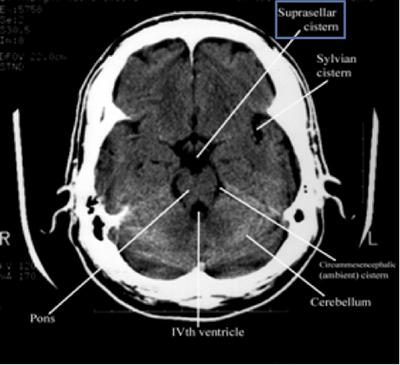

Step 2: Cisterns

Cisterns

Cisterns are the compartments within any of the openings in the subarachnoid space of the brain filled with cerebrospinal fluid. Two key questions to answer regarding the four key cisterns (Circummesencephalic, Suprasellar, Quadrigeminal and Sylvian)

• Is there blood?

• Are the cisterns open?